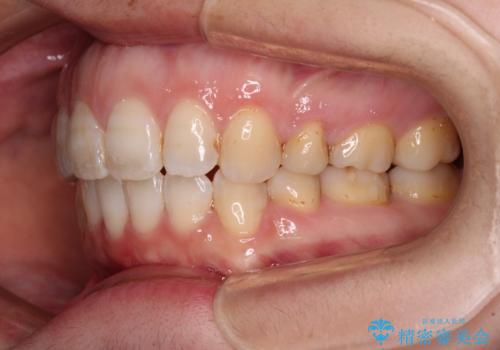

- 口元の閉じにくさと、前歯のでこぼこの歯並びを気にして来院された患者様です。

口元を積極的に引っ込めるために、上下左右の小臼歯計4本を抜歯することとしました。

セオリーでは第一小臼歯を抜歯しますが、上下右側は第二小臼歯に銀歯が装着されているため、第二小臼歯を抜歯することとしました。

積極的に前歯を牽引したことで、口元の閉じにくさは顕著に改善され、横顔のシルエットが大幅に変化しました。